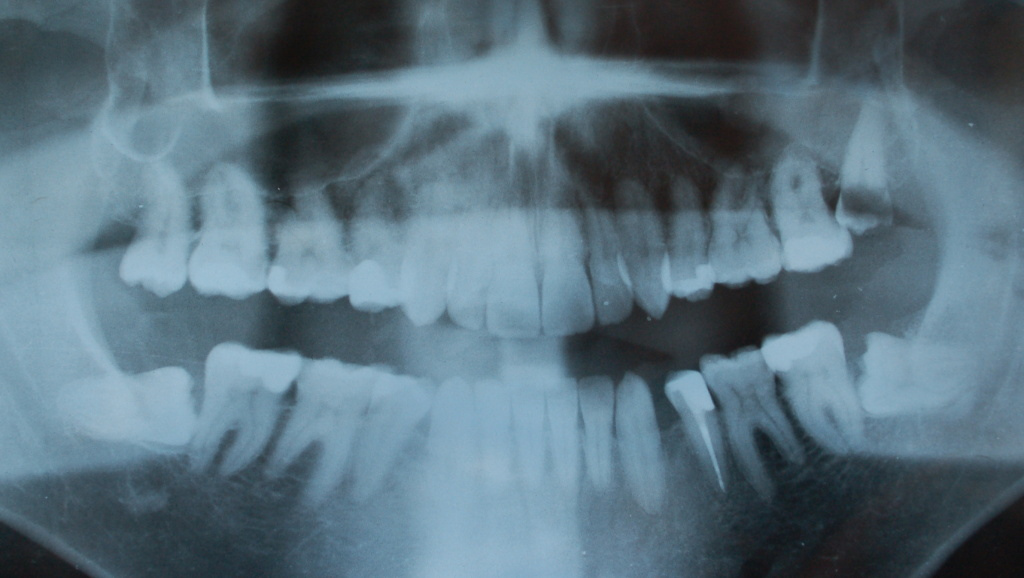

Hablemos sobre las muelas del juicio, desvelaremos por qué son denominadas de esta manera y cuál es su función en nuestro organismo. A lo largo de nuestra vida, es probable que hayamos escuchado sobre las muelas del juicio y sus implicancias en nuestra salud bucal. Sin embargo, pocos conocen el origen de su nombre y la importancia que estas piezas dentales tienen en nuestra boca.

Para solucionar este problema, la extracción de las muelas del juicio problemáticas es la mejor opción. Si estas muelas están causando molestias o están afectando la posición de otros dientes, es recomendable acudir al dentista para evaluar la necesidad de extraerlas. La extracción de las muelas del juicio se realiza de forma sencilla y segura, y generalmente no tiene repercusiones negativas en nuestra mordida o en el mantenimiento bucal.